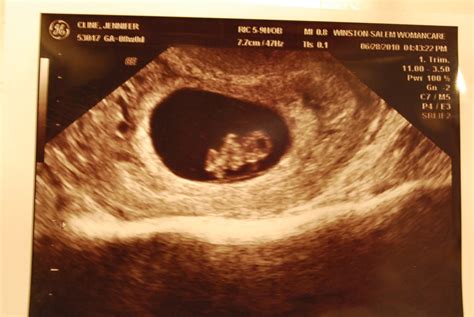

An 8 weeks pregnant sonogram is typically performed transvaginally to get a clearer view of the uterus and the developing embryo. Here are some key points to expect:

• Embryo Size: At 8 weeks, the embryo is about the size of a raspberry, measuring approximately 16 to 18 millimeters in length.

• Heartbeat: One of the most exciting moments is hearing your baby's heartbeat. By this week, the heartbeat is usually detectable and can be seen on the sonogram.

• Developmental Milestones: The embryo's tail is disappearing, and the head makes up nearly half of the embryo's length. The neural tube, which will develop into the brain, spinal cord, and nervous system, is closing.

• Organ Formation: The early stages of organ development are visible. The heart is beating more strongly, and the liver, pancreas, and lungs are beginning to form.

During the sonogram, the technician will also check for any potential issues, such as ectopic pregnancy or miscarriage. This is a crucial step in ensuring the health and safety of both you and your baby.